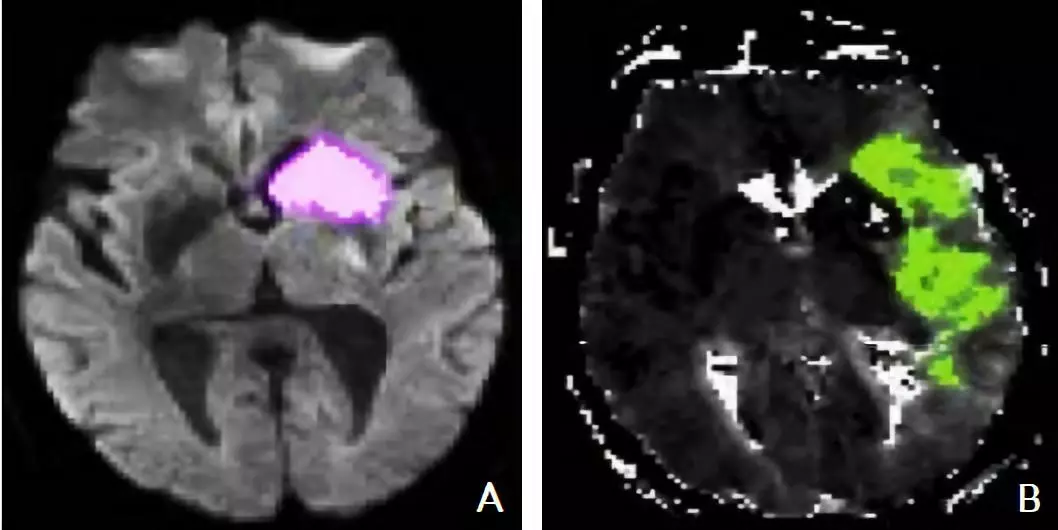

5.2.3 磁共振成像DWI-PWI不匹配区

MRI PWI常采用动态磁敏感对比增强技术,通过对比剂团注追踪技术进行动态增强扫描,依靠对比剂磁化率改变引起信号变化的原理成像。经处理后可得出相应灌注成像的参数如CBF、CBV、MTT及TTP等。研究表明,CBF下降和MTT延长是组织缺血的相对敏感指标,但存在过分估计最终梗死体积的可能性;TTP图像上脑灰质、白质之间无明显区别,可以清楚显示病变的范围和边界。虽然目前识别缺血半暗带的方法有多种,但MRI DWI与PWI不匹配区是急诊过程中判断缺血半暗带较切合实际的方法(图4)。一项回顾性研究认为,PWI的病灶面积是DWI病灶面积的2.6倍时早期再灌注的治疗效果最好[71]。

图4. 磁共振成像DWI-PWI不匹配区影像

注:A:磁共振DWI序列:高信号的梗死区(粉色标记区);B:磁共振PWI序列:梗死区周围的缺血半暗带(绿色标记区)。DWI:弥散加权成像;PWI:灌注加权成像